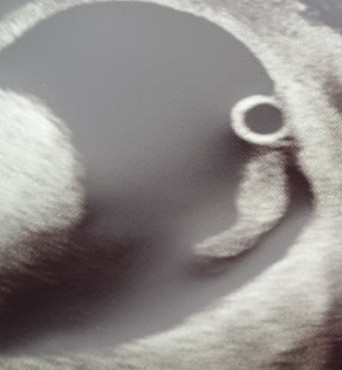

Anne1987 · 18/05/2021 17:09

I am still shell shocked, that despite the pain, blood, and cessation of symptoms (including my breasts going back to normal after increasing in size)- our sweetpea is still going strong (measuring now at 7 weeks 4 days, but that is what I thought I was anyway, with hcg of just over 238000). Here is the little pickle, who has had Mum (and Dad) very worried. I have been told to not worry with any further pain, blood or lack of symptoms - unless the blood clots. So I am going to try and hold strong for the 12 week scan. I hope this helps others who may come across this in the future and give some hope, as you have all been so reassuring to me and have made these last few weeks more manageable x